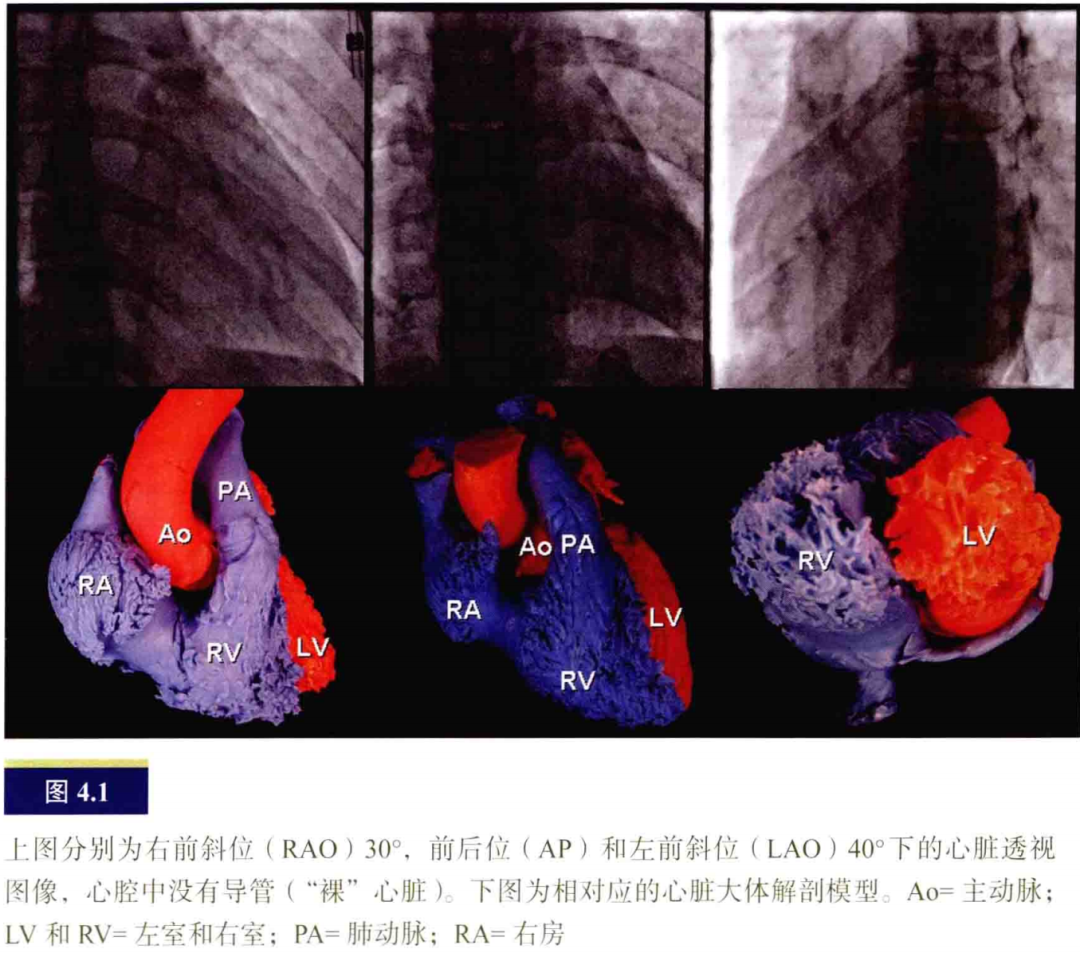

在有创电生理(EP)检查之前,电生理医生需要通过评价个体患者的常规透视影像来辨认心脏解剖。然而,心脏以及心脏周围特殊的毗邻关系不容易被观察到,因为心脏组织于透视下仅为阴影。图4.1中,分别是右前斜位(RAO)30°、前后位(AP)和左前斜位(LAO)40°下的心脏透视图像和相对应的心脏大体解剖模型。如果仅仅观察心脏轮廓,心脏中特殊点的准确位置很难确定。